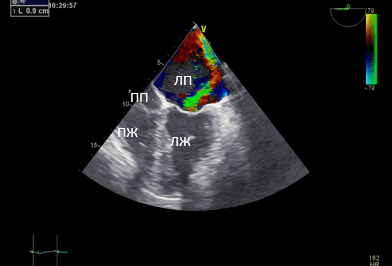

Данные интаоперационной 3D ЧП ЭхоКГ: Митральный клапан: ФК 44 мм, створки уплотнены, расщепление передней створки от свободного края до фиброзного кольца в сегменте А 2, движение створок разнонаправленное. Градиент давления максимальный — 6,2 мм рт.ст., средний 2,1 мм рт.ст. Регургитация выраженная: vena contracta - 0,9 см, площадь потока регургитации — 11,4 см², в непрерывноволновом допплеровском режиме плотный поток регургитации, радиус PISA — 1,0 см. Регургитация — эксцентричная, по боковой стенке ЛП.

Рис. 3. Чреспищеводная эхокардиография. Среднепищеводный доступ. Четырёхкамерная позиция. Vena contracta 0,9 см.